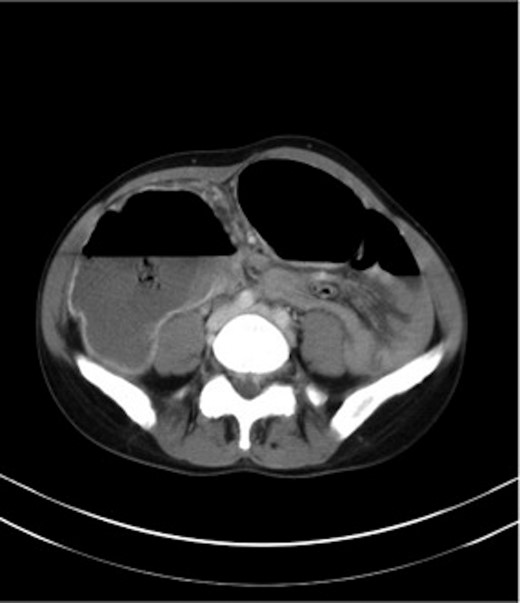

Haemoglobin was 12.6 g/dl and a WCC of 8.3 × 109/l. Other remarkable laboratory tests included a CRP of 19 mg/l. Urinalysis was normal. The AXR revealed a grossly distended large bowel. A CT scan of the abdomen revealed that the rectum, sigmoid and descending colon were collapsed with an apparent calibre change within the transverse colon with no mass lesion (Fig. 3).

CT of the abdomen (Case 2) showing a calibre change within the transverse colon with no mass lesion.

A gastrografin enema (Fig. 4) failed to demonstrate any flow beyond the mid-transverse colon. A presumptive diagnosis of transverse colon obstruction was made and the patient was taken to theatre.